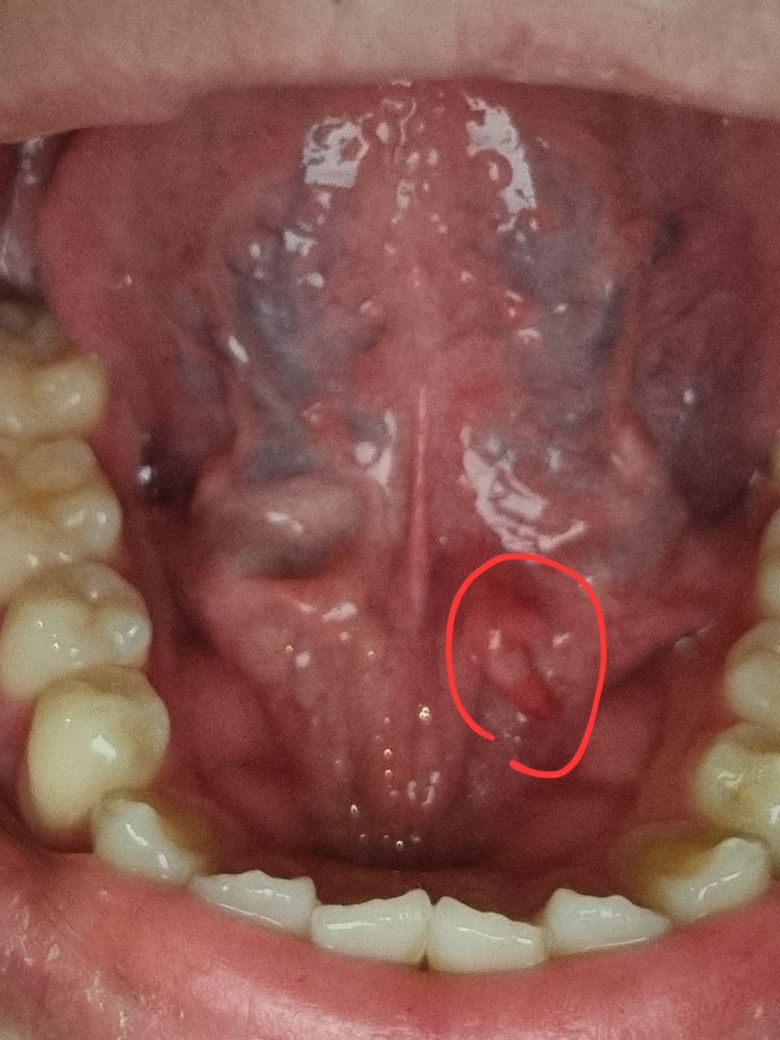

혀 안? 쪽에 뭐가 났어요 아프진 않은데 너무 거슬립니다

제목 그대로 혀안에 뭐가 났습니다

아프진 않지만 계속 느껴져서 거슬립니다. 뭔가 덜렁거리는 것처럼 거슬립니다. 혹시 무엇일까요? 병원을 가야한다면 어디로 갈까요

적어주신 증상으로 미루어 구내염의 가능성이 생각되나 올려주신 사진이 또렷하지 않아 불편감이 지속된다면 이비인후과 진료를 받을 것을 권합니다.